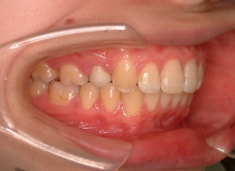

治療後(1年9ヶ月後)